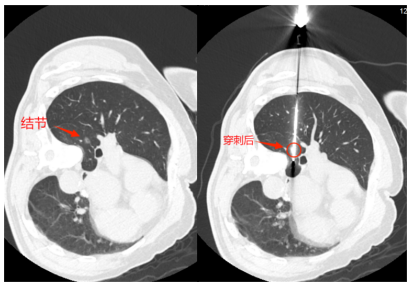

治疗过程中胡主任通过CT引导精准穿刺至肺结节(仅有1cm)核心位置,在迅速降温至-196.0℃后,肺结节周围初步形成冷冻消融的界限。

△穿刺位置非常精准